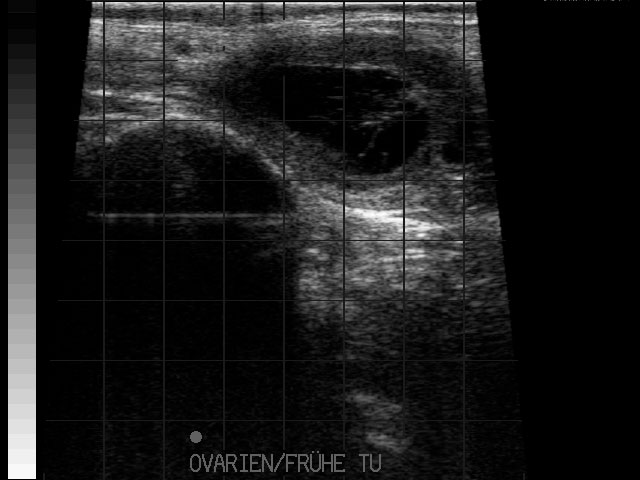

Eierstockstumor

Frühe Resorption